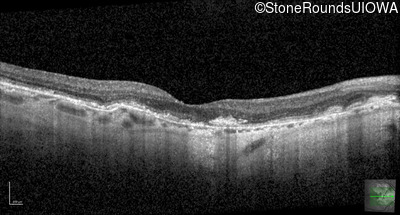

Optical Coherence Tomography - Right - 20/20 -2

Exemplar / OCT Stack